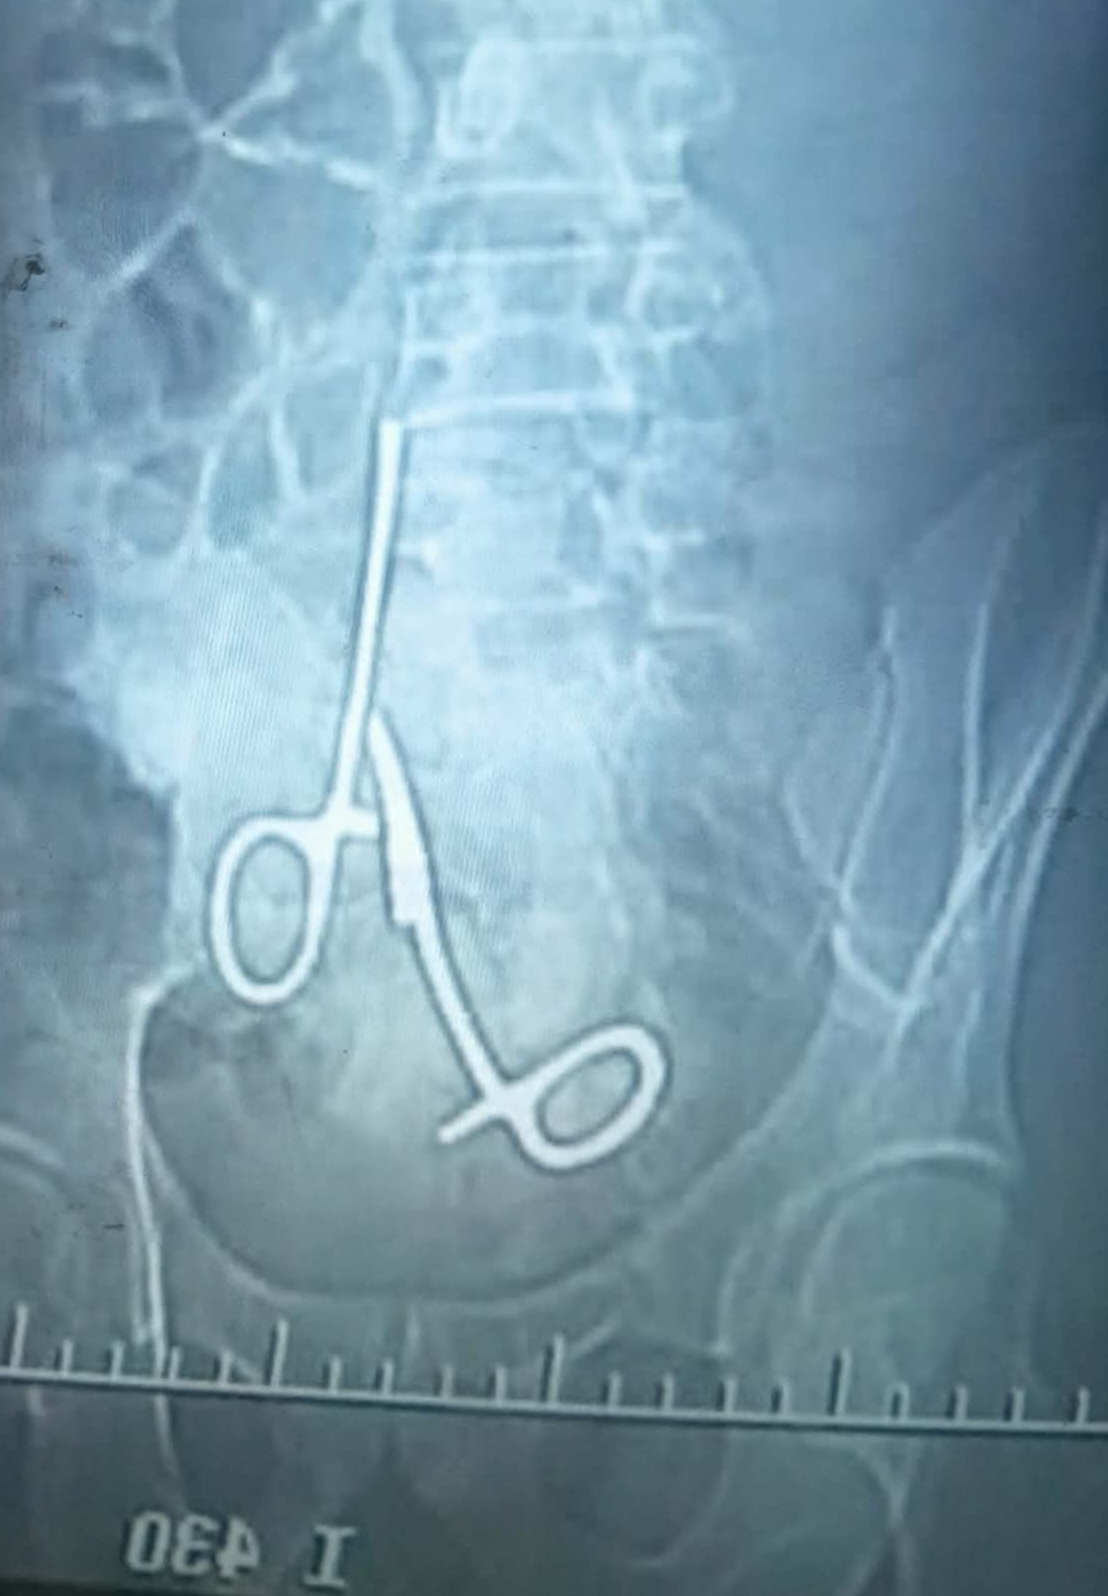

بسبب خطأ طبي، مقص يظل تسع سنوات ببطن مريض

تسع سنوات من الألم والمعاناة قضاها المريض م. ص من منطقة الشقلة بولاية الجزيرة . بسبب خطأ طبي، بعد اجرائه…